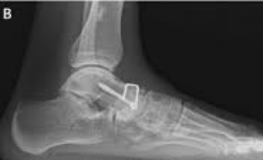

Talonavicular arthrodesis involves removing the remaining cartilage from the talonavicular joint and positioning the talus and navicular bones in proper alignment. The joint is then stabilized with screws and/or plates to allow the bones to fuse together into a single, stable unit.